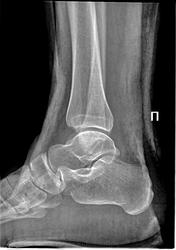

Коллеги, прошу откликнуться и поучаствовать. Дама 35лет, какая-то травма голеностопа, очередной контроль. Непонятен механизм и субстрат изменений таранной кости.

Это 28.03.2013г. Коллега пишет компрессионный перелом таранной кости.

По СКТ между снимками - болезнь Диаза, перелом "задней лодыжки" без смещения. Визуального ряда СКТ нет.

Это 13.05.2013г. Другой коллега подтверждает Диаза.

Я весь в сомнениях. Случай не у меня, на глаза попался случайно. Заранее благодарен.